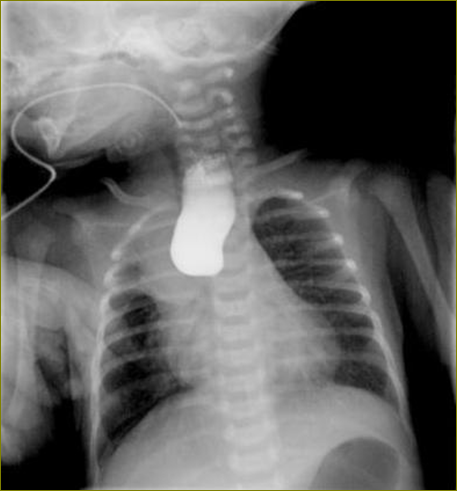

1021日对李老汉一家而言一个幸福的日子,家中迎来了一位新成员——他们的儿子出生了。李老汉还沉浸在老来得子的天伦之乐中,然而厄运紧随其后,他们很快就发现宝宝一吃奶就吐,当地医院的一张上消化道造影片子这个无辜的小生命判了“死刑”——先天性食管闭锁,气管食管瘘。这个噩耗如晴天霹雳一般落在了李老汉的头上,命运的嘲弄让李老汉一下子懵了。

先天性食管闭锁是一种新生儿期消化道的严重发育畸形,80%以上合并气管食管瘘,即III型食管闭锁。主要表现为吃奶时出现呕吐、青紫、呛咳和呼吸困难等症状。新生儿口周看起来就像螃蟹嘴一样,一直在吐泡泡。

在我院心胸外科吴国伟副主任医师刚见到这位小生命时,患儿重度脱水,身体重度营养不良,经检查发现肺部感染重、右肺上叶不张,白细胞21.7*10^9/L,情况十分危急。新生儿科医师立即给予营养支持抗感染治疗,并积极开展各项术前准备。在听到医生说孩子还有救,到医护人员对他的小宝贝如此精心呵护万分焦急的李老汉也稍稍松了一口气但仍然愁眉不展的神情也透露着他内心的难言之隐。原来李老汉的家境并不富裕,他担心儿子手术费用让这个本就拮据的家庭雪上加霜。了解到老汉心事后吴主任告诉老汉目前食道闭锁矫治、食管气管瘘结扎术”在们医成功率较高,手术费用也比较低,如果李老汉在经济方面真的有困难,可以帮助他申请医院慈善基金的资助。吴主任番话像是让老汉吃了颗定心丸,紧锁的眉头也渐渐舒展了开来

图为患儿术前食道造影